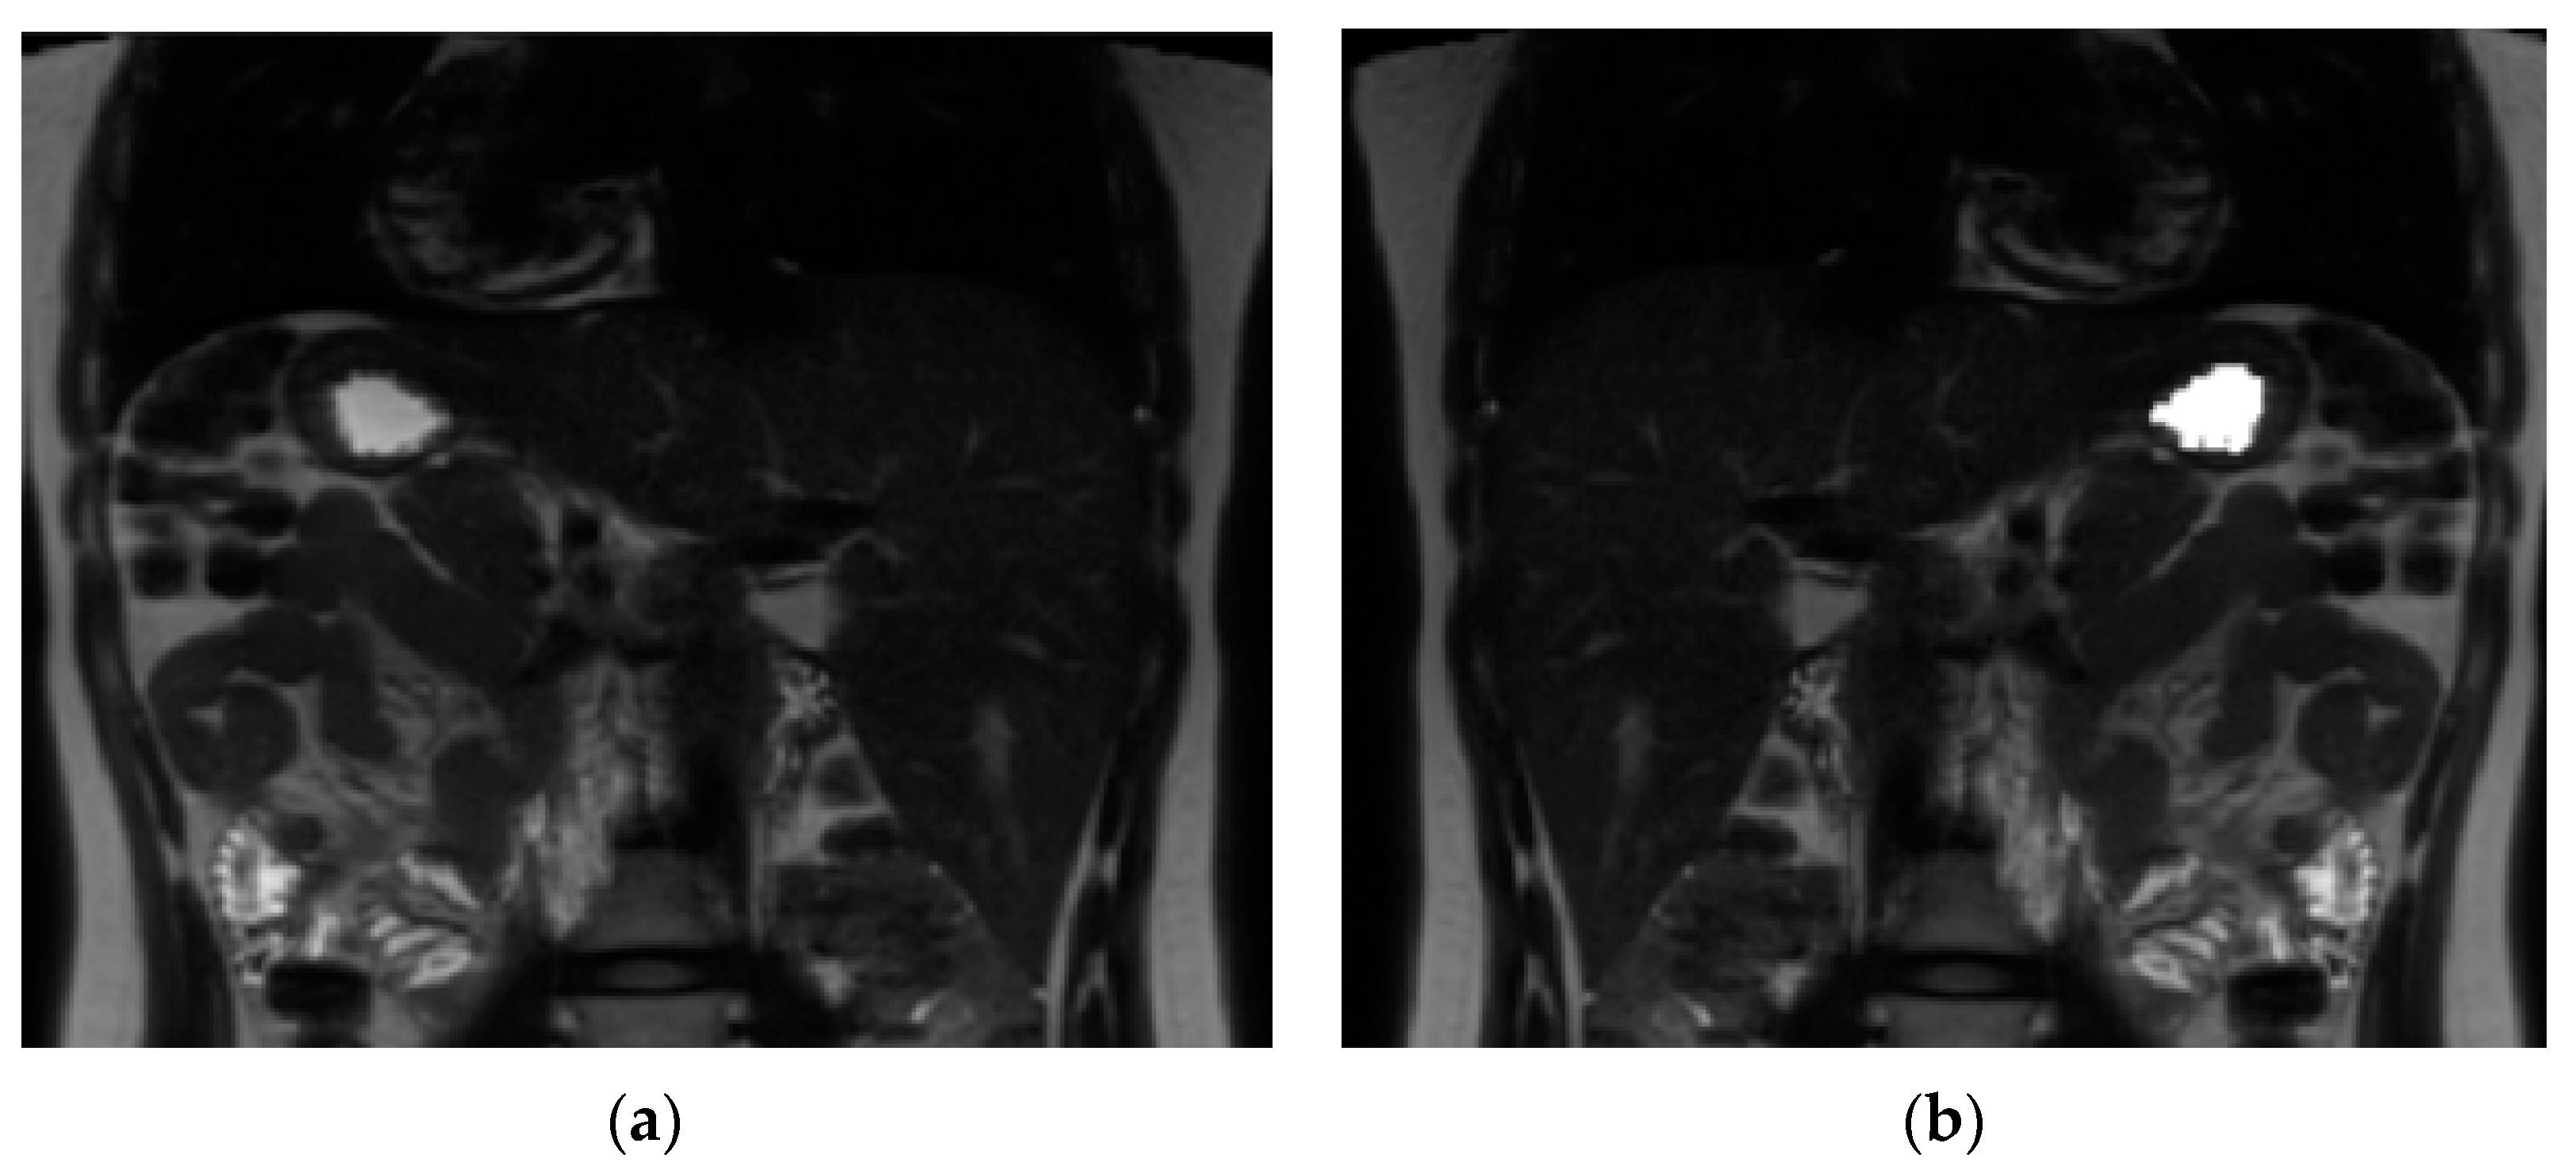

2.7. Image Analysis